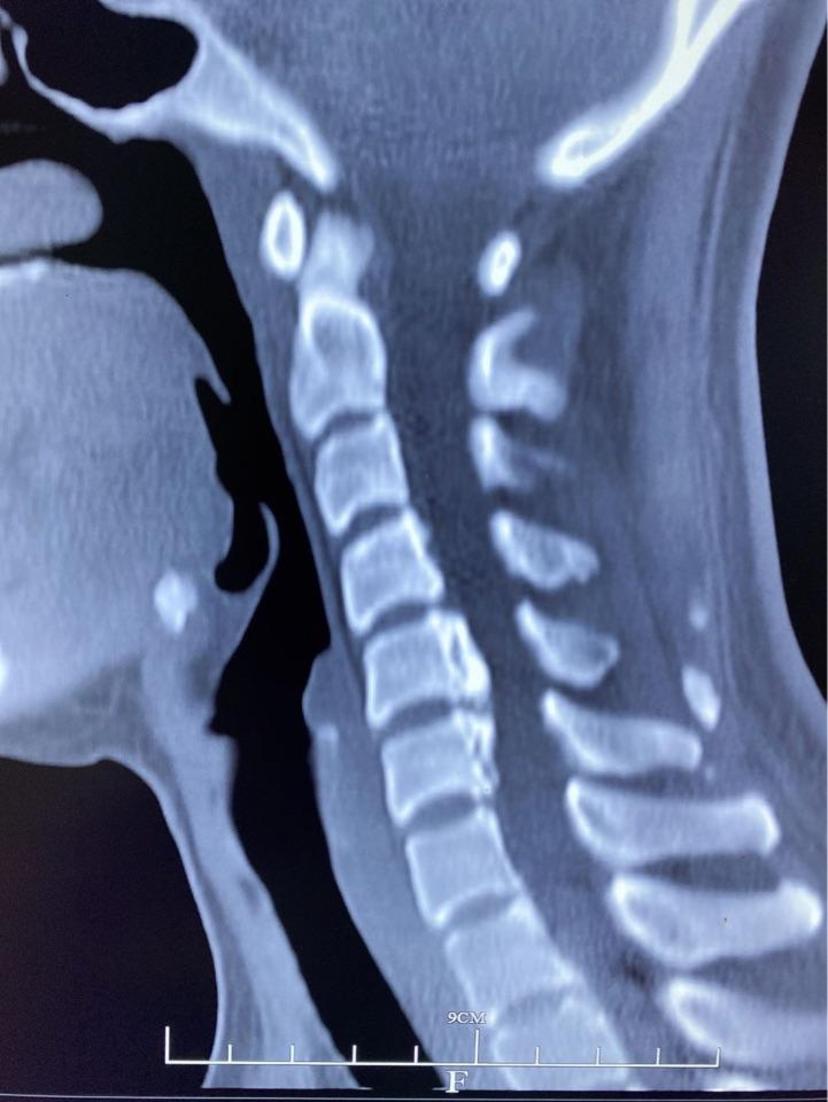

患者颈痛10年,诊断颈椎病,曾多次给予针灸、小针刀、口服药物等治疗,效果不明显,手麻及行走不稳逐渐加重,经CT及磁共振检查后,诊断两节段椎间盘突出合并严重后纵韧带骨化,经前路ACCF微创手术,完全去除了压迫神经脊髓的物体,术后当晚明显感到四肢力量增大,麻木感好转,第二天自行下地行走,第三天康复出院!两节段颈椎间盘突出

后纵韧带骨化压迫脊髓